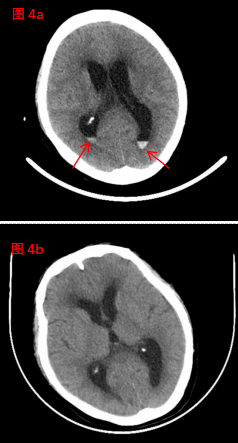

在神經(jīng)外科與腎病科的通力協(xié)作和精心救治下,患者精神狀態(tài)逐漸改善、飲食睡眠不斷好轉(zhuǎn),住院40天后,恢復(fù)良好,復(fù)查顱腦CT(圖4b)較入院時(shí)(圖4a,紅色箭頭處指示顱內(nèi)血腫)明顯吸收?;颊咝凶咦匀纾瑵M意出院!(神經(jīng)外科、宣傳科)